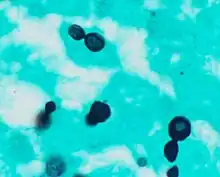

Histopathology of Histoplasma capsulatum, GMS stain, showing narrow budding yeast Histoplasma capsulatum var. duboisii, methenamine silver stain

Histoplasma capsulatum var. duboisii, methenamine silver stain Macroconida form of Histoplasma capsulatum